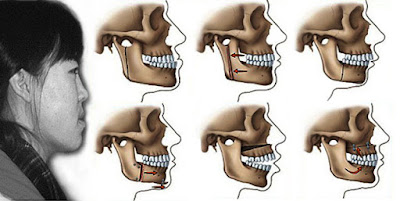

Niềng răng trước hết có thể điều trị răng móm. Tuy nhiên, trên thực tế không phải loại răng móm nào cũng có thể niềng răng hiệu quả được. Biểu hiện của móm rất dễ nhận biết đó là: xương hàm dưới nhô ra phía trước, khi thả lỏng miệng răng hàm dưới phủ ngoài răng hàm trên, cằm bị lệch.

Để thuận tiện cho việc chuẩn đoán và lựa chọn phương pháp điều trị móm được chia thành 3 dạng chính: móm do răng, do xương hàm hoặc do cả xương hàm và răng.

Móm do răng

Với dạng móm này vấn đề chính nằm ở phần răng cửa, phương pháp điều trị đơn giản. Tuy nhiên, nếu không được phát hiện sớm và điều trị kịp thời thì phần răng và xương hàm trên sẽ bị ảnh hưởng. Khiến cho răng của hàm trên kém phát triển, làm gương mặt bị gãy, trông mất thẩm mỹ. Bác sĩ thường chọn phương pháp niềng răng móm để điều trị cho trường hợp này gồm có niềng răng tháo lắp và niềng răng cố định.

Móm do xương hàm

Có thể do hàm trên kém phát triển, hàm dưới phát triển quá mạnh, hoặc do dị tật khe hở vòm miệng làm xương hàm trên thiếu hụt kích thước khiến cho răng hàm trên luôn ở phía trong so với răng hàm dưới. Để điều trị móm do xương hàm cần phải phẫu thuật tạo hình, phương pháp này mang lại cho bạn một hàm răng đẹp chỉ sau một lần điều trị. Phẫu thuật móm được ưa chuộng trên thế giới, bởi bên cạnh yếu tố thẩm mỹ, nó còn đảm bảo về sự an toàn, không làm ảnh hưởng tới chức năng vùng răng, hàm, mặt.

Móm vừa do hàm vừa do răng

Với trường hợp móm do cả 2 nguyên nhân này thì cần kết hợp niềng răng trước để đảm bảo tính thẩm mỹ toàn diện sau phẫu thuật. Phẫu thuật điều trị móm chỉ áp dụng cho những người từ 18 tuổi trở lên. Vì ở độ tuổi này, các dấu hiệu tăng trưởng của xương hàm đã ngừng lại và sai lệch của khuôn mặt không còn tiếp tục.